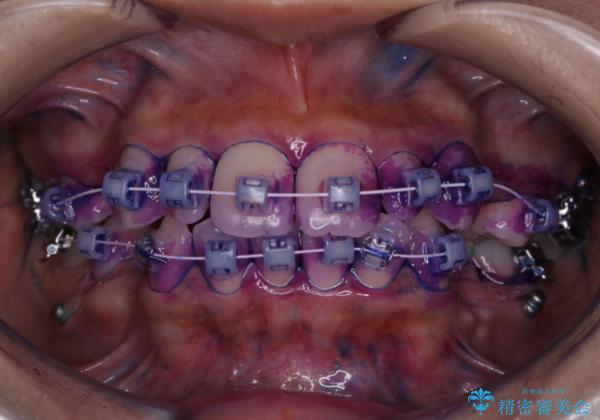

ワイヤー矯正中のクリーニング PMTC

- ワイヤー矯正中にクリーニングを行いたいとのことで来院されました。PMTC60分コースでと歯磨き指導も行いました。

ワイヤー矯正中はブラッシングが難しくなるため、磨き残しが多くなることがあります。適切な道具を使って、適切なブラッシング方法を習得することで、磨き残しを減らすことができます。

また、矯正で歯の移動があると今までなかったところに隙間が出てきたり、ガタつきが解消されてきたりすることで、お口の中の環境が変わります。そのため、定期的に専門的な機械・材料を使用したProfessinnalcleaning(pmtc)を行うことがおススメです。